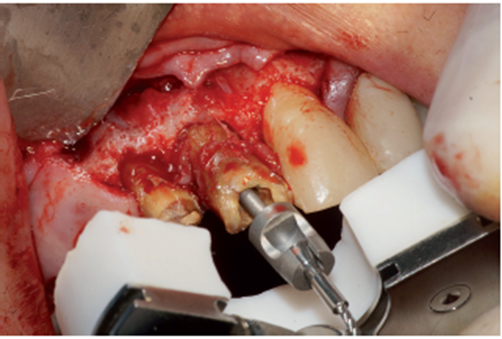

O procedimento cirúrgico foi iniciado através de uma anestesia infiltrativa com articaína 4%. Foram realizadas incisões relaxantes (Figura 4) para expor o leito cirúrgico e, consequentemente, a lesão periapical (Figura 5). Após o deslocamento do retalho, foi realizada a exodontia de forma atraumática (Figura 6) e na sequência, foi feita a curetagem do alvéolo removendo todo o tecido de granulação (Figura 7). Uma vez realizada a toalete do leito cirúrgico (Figuras 8 e 9), o implante Cone Morse Due Cone de 3.5 X 13 mm (Implacil De Bortoli) foi instalado seguindo o melhor posicionamento dentro do rebordo residual, conforme planejado (Figuras 10 e 11). Em sequência, foi realizada a instalação do Cover Screw (Figura 12) e o preenchimento do defeito ósseo com biomaterial (Bio-Oss 0,25), conforme figuras 13 e 14). O fechamento foi realizado com membrana de PTFE-d (Cytoplast TXT–200, Osteogenics – Lubbock TX, EUA), customizada para ser adaptada sobre o defeito ósseo, estendendo-se de 3 a 5 mm da margem do defeito ósseo e intencionalmente exposta (Figura 15). A sutura foi realizada com fio de PTFE (Cytoplast), como podemos observar na figura 16, e instalado um provisório adesivo na região (Figura 17).